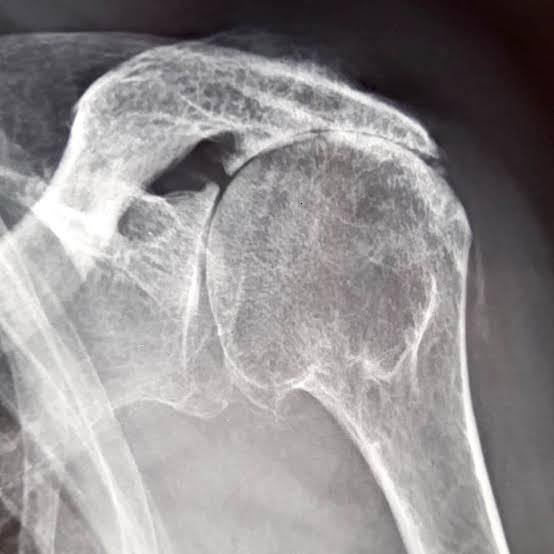

Radiographie d'une arthrose de l'épaule centrée

Radiographie : Arthrose centrée de l'épaule

La radiographie standard : face, profil, rotation interne/externe

Elle va apporter une grande partie des informations nécessaires pour évaluer l'arthrose de l'épaule :

• Pincement de l'interligne articulaire (entre la tête humérale et la glène de l'omoplate)

• Condensation de l'os sous-chondral

• Ostéophytes (inférieur, antérieur, postérieur…) - intérêt +++ des clichés en rotation interne/externe

• Forme de la tête humérale (aplatissement, perte de sphéricité…)

• Géodes, lacunes intra-osseuses

• Centrage de la tête humérale (l'excentration avec surélévation serait en faveur d'une lésion associée de la coiffe des rotateurs)

• Évaluation du stock osseux (surtout sur la glène de l'omoplate)